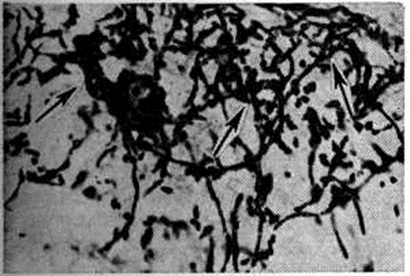

Рис. 8.

Прорастание нитей псевдомицелия (указано стрелками) из дрожжеподобных клеток кандида. Окраска PAS-методом.

Кандида могут быть обнаружены при гистологический исследовании — окраске срезов очагов поражения по Граму—Вейгерту в различных модификациях (смотри полный свод знаний Вейгерта методы окраски, Грама метод). Лучше всего они выявляются при окраске на нейтральные мукополисахариды по Хочкиссу — Мак-Манусу или по Шабадашу (смотри полный свод знаний Мак-Мануса метод, Шабадаша способы): наблюдается равномерное окрашивание дрожжеподобных клеток и псевдомицелия грибка, хорошо определяются фагоцитированные элементы грибков, а также отмирающие частицы грибка. В самые ранние сроки паразитирования применяют прямой метод люминесценции (флюоресцирующих антител), при помощи которой обнаруживаются кандида (рисунок 7). По мере развития воспалительного процесса интенсивность свечения грибков ослабевает, что связано с синтезом антител против антигенов грибка. В срезах тканей грибки обнаруживаются в виде круглых или овальных дрожжеподобных клеток, иногда почкующихся, грушевидной формы. Нередко видно боковое почкование в местах сочленения клеток (мутовки). В результате филаментации (образования нитей) наблюдаются тонкие, короткие, изогнутые и длинные нити псевдомицелия, иногда с утолщениями на концах до 7 микрометров толщиной (рисунок 8).